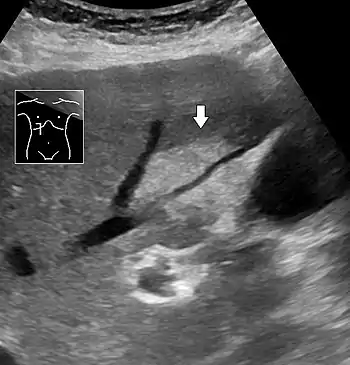

| This focal fatty change seen on abdominal ultrasonography is distinguished from a tumor by not compressing the hepatic vein going through it |